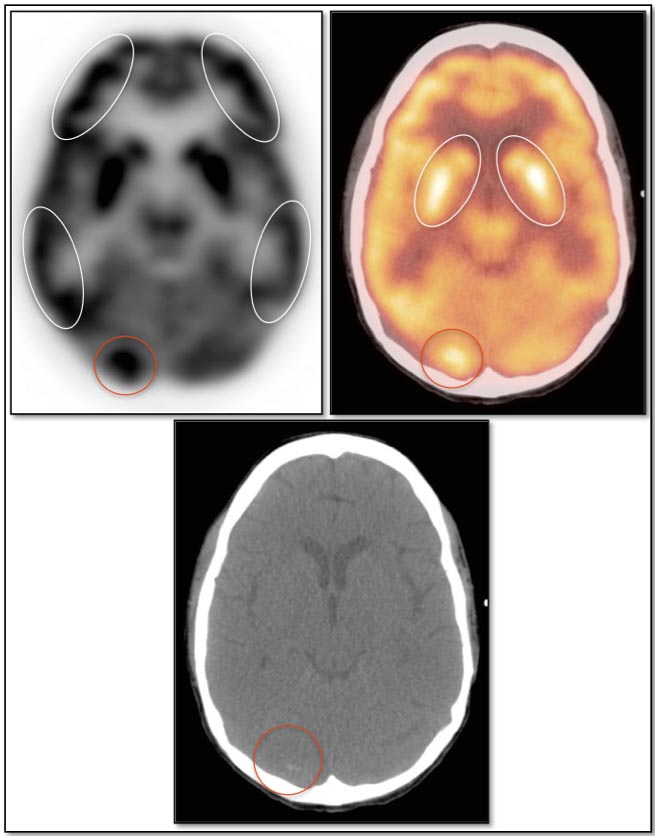

Brain

As the brain fully relies on glucose metabolism, it demonstrates rather diffuse intense uptake of FDG. In fact, its metabolic activity is so intense, that most PET reading software programs will require the reader to manually decrease its intensity to evaluate the brain for potential lesions.

Familiarity with the normal symmetric uptake of FDG in the brain will help the reader identify primary brain tumors and metastatic lesions.

Areas of normal relative increased uptake include the grey matter, basal ganglia, frontal eye fields, posterior cingulate gyrus and visual cortex. Symmetry of uptake should be preserved.

As most cases begin at the skull base, careful attention must always be paid to the sella.